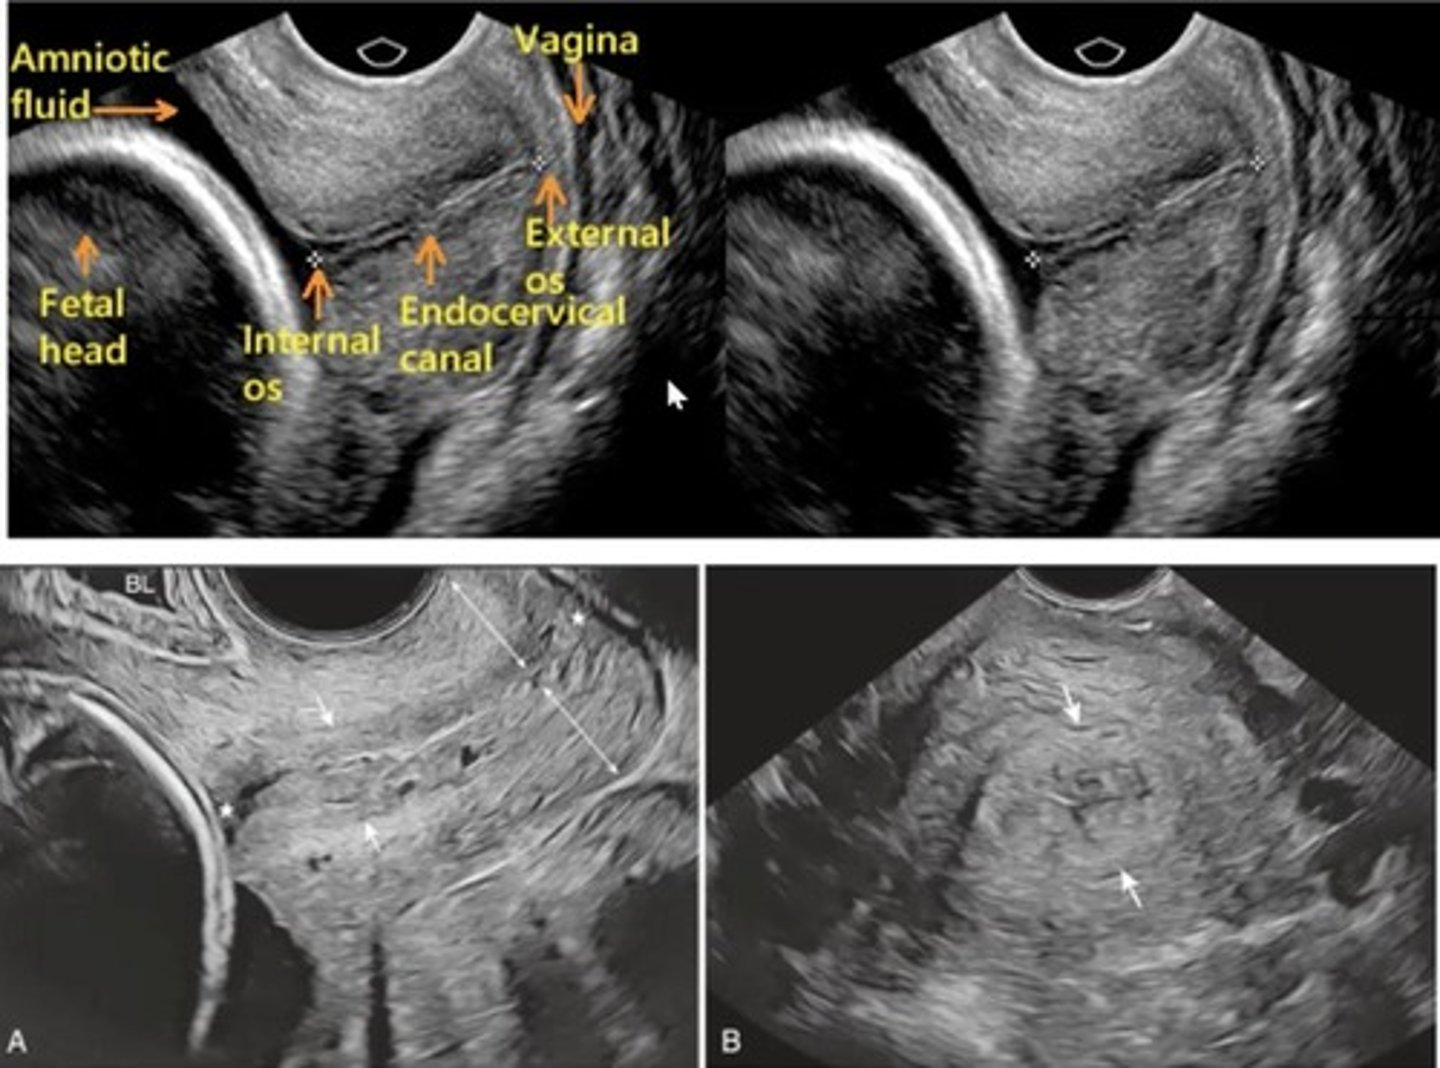

Name 2 pitfalls of TAS of the cx.

- Overdistended bladder can artificially elongate the cx length by compressing it

- Empty bladder

- Low amniotic fluid

- Low fetal head (cranium shadows over cx)

- Uterine contractions may falsely elongate cx (wait for 15 mins)

What U/S method is the gold standard for measuring the cx?

Transvaginal ultrasound

What are the 2 pitfalls of measuring the cx using TVS?

- Excess pressure elongates cx (see if ant and post lips have equal thickness)

- Dynamic cx: responds to pressure changes on cx (applying manual pressure to uterine fundus for 15 secs then let go, evaluate uterus for 5 mins to see any changes in length of cx)

What is funneling of internal os? What are abn widths and lengths of the funnel?

- Dilation and herniation of membranes into cervical canal

- Width of the funnel - more than 8mm (TAS) or 5mm (TVS) = abn

- Length from top to bottom of funnel = more than 3-6 mm = abn